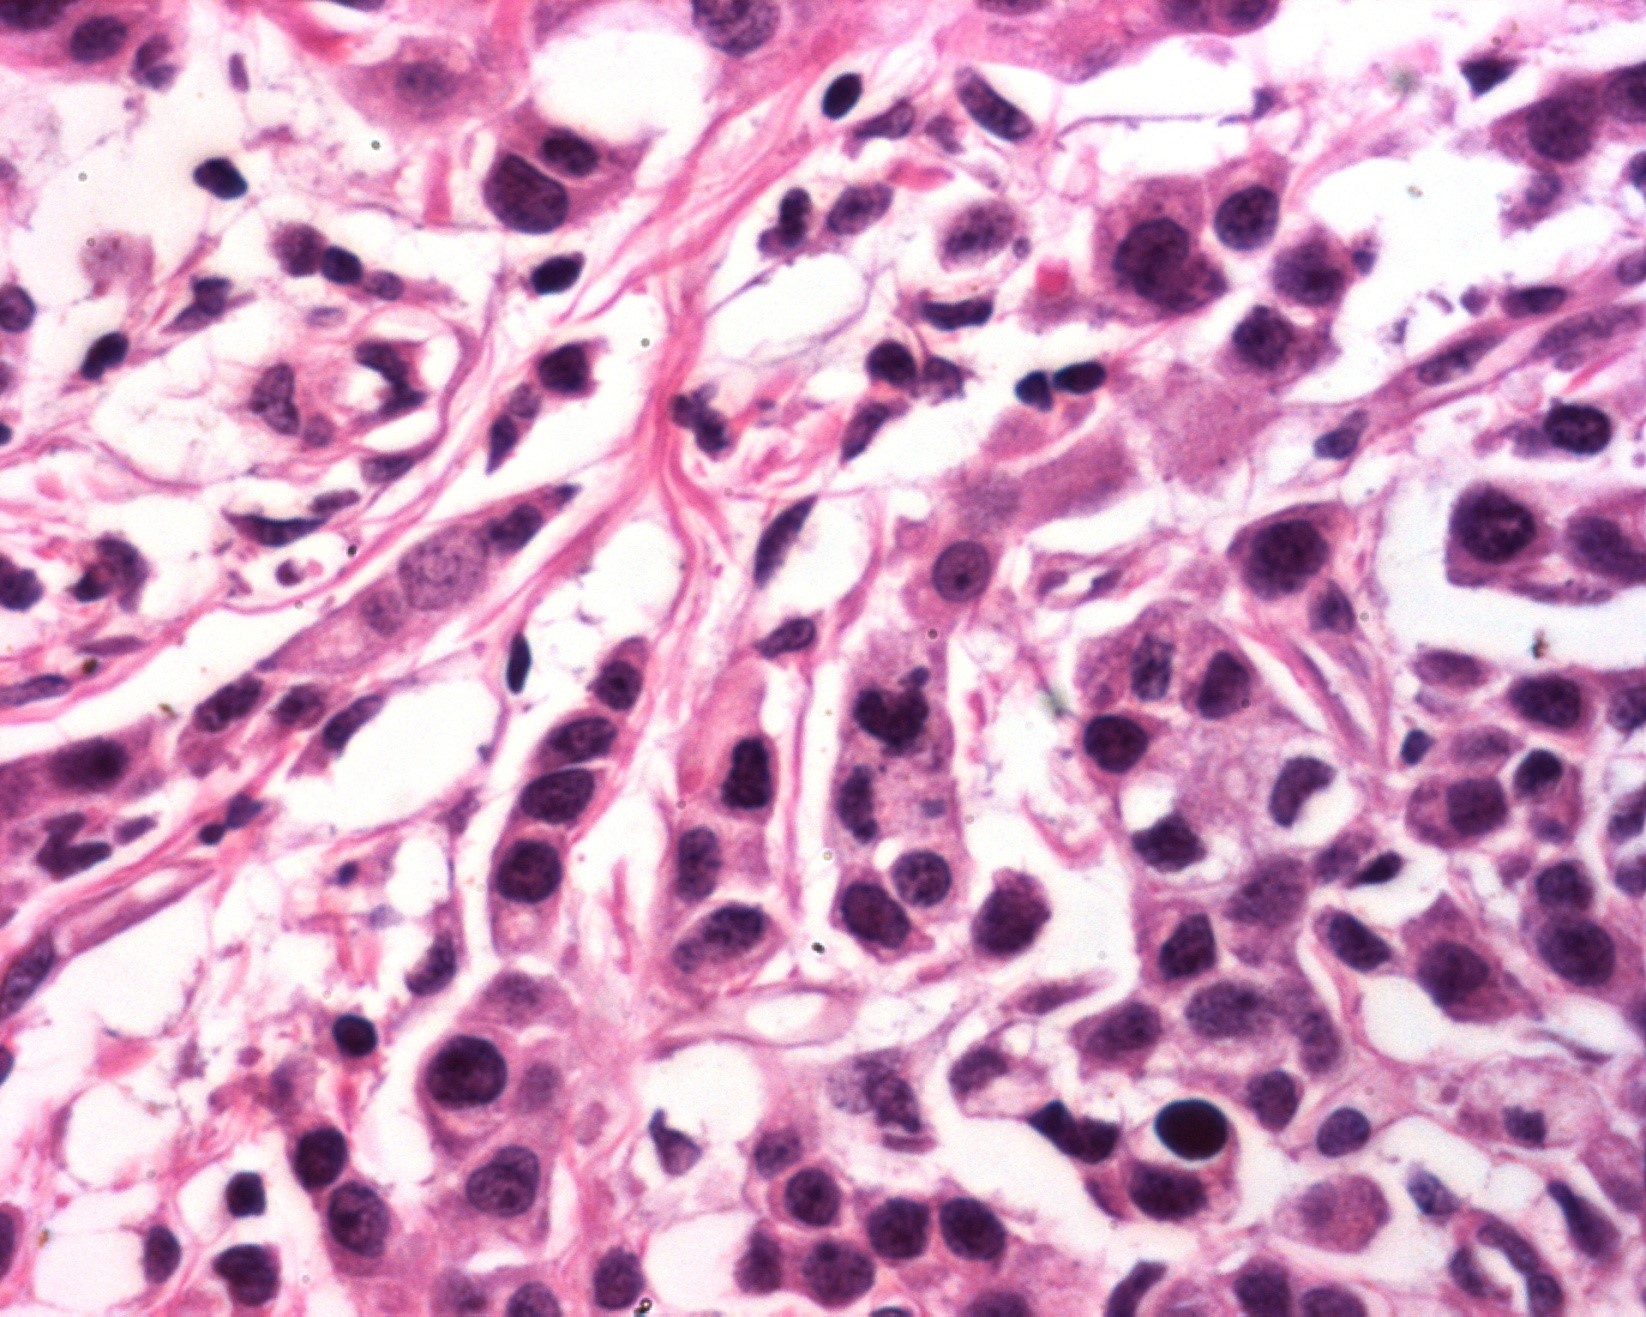

Cortes histológicos de nódulos en axila:

Carcinoma metaplásico productor de matriz o de tipo mixto, con respuesta categoría I de RCB o Miller y Payne 3.

El perfil hormonal se ha asociado con menor sobrevida en estas pacientesm, así como el estado ganglionar y la invasión linfovascular: